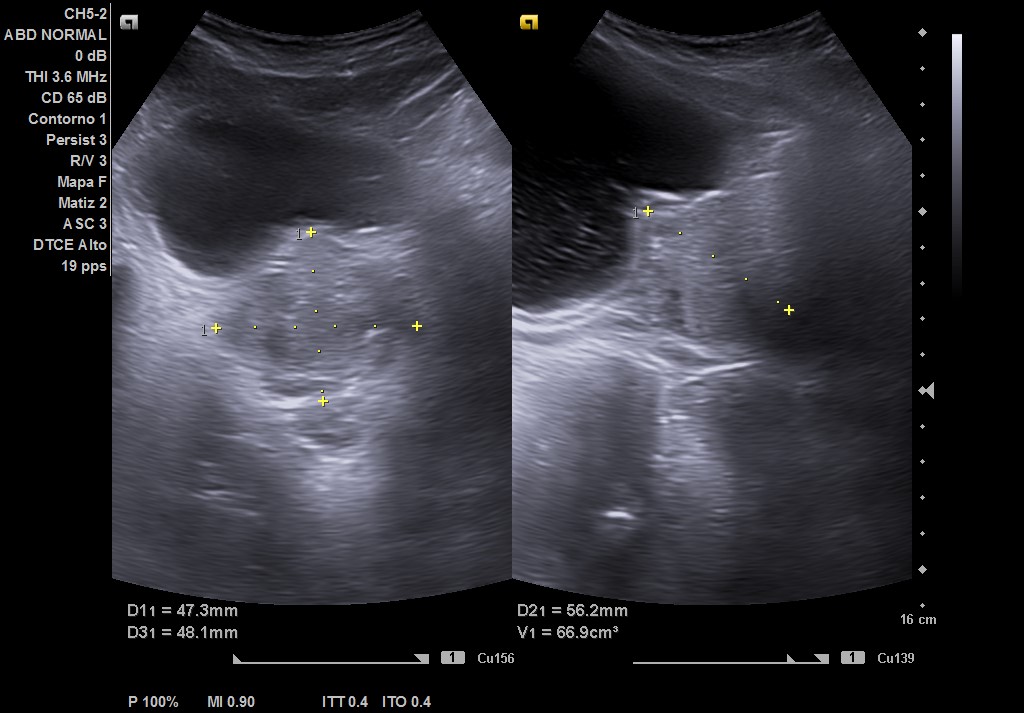

Ecografía tras ingerir 1 litro de agua y sin orinar posteriormente, con sonda convex: se visualiza vejiga repleccionada hasta 2 cm del ombligo, con > 550 cc (difícil de cuantificar por gran tamaño). Residuo postmiccional 525 cc, paredes de vejiga con signos de lucha, divertículo e imagen de «centelleo» en desembocadura de uréter derecho, pero sin afección del jet ureteral ipsilateral. Próstata de 67 cc aproximadamente, que protruye en vejiga. Riñones con ecoestructural normal sin dilatación en vía excretora.

• Ecografía en Urología: pared vesical engrosada difusa con trabeculación, grandes cálculos de 14, 10 y 9 mm. Próstata 48 gr con pequeña imagen quística de 10 mm.